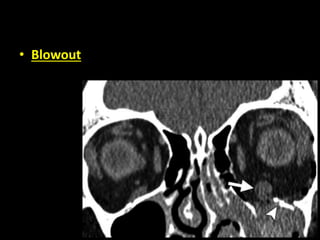

• Blowout